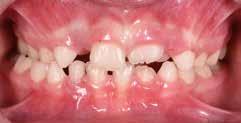

B.M. Bambina di sei anni e mezzo, con malocclusione scheletrica di II Classe, deep-bite over-jet elevato, lieve contrazione dell’arcata superiore, alterazione dell’eruzione dell’elemento dentale 21.

Fig. 122 > Immagine intraorale frontale.

Fig. 123 > Immagine intraorale laterale destra.

Fig. 124 > Immagine intraorale laterale sinistra.

Fig. 125 > Immagine occlusale superiore.

Fig. 126 > Immagine occlusale inferiore.